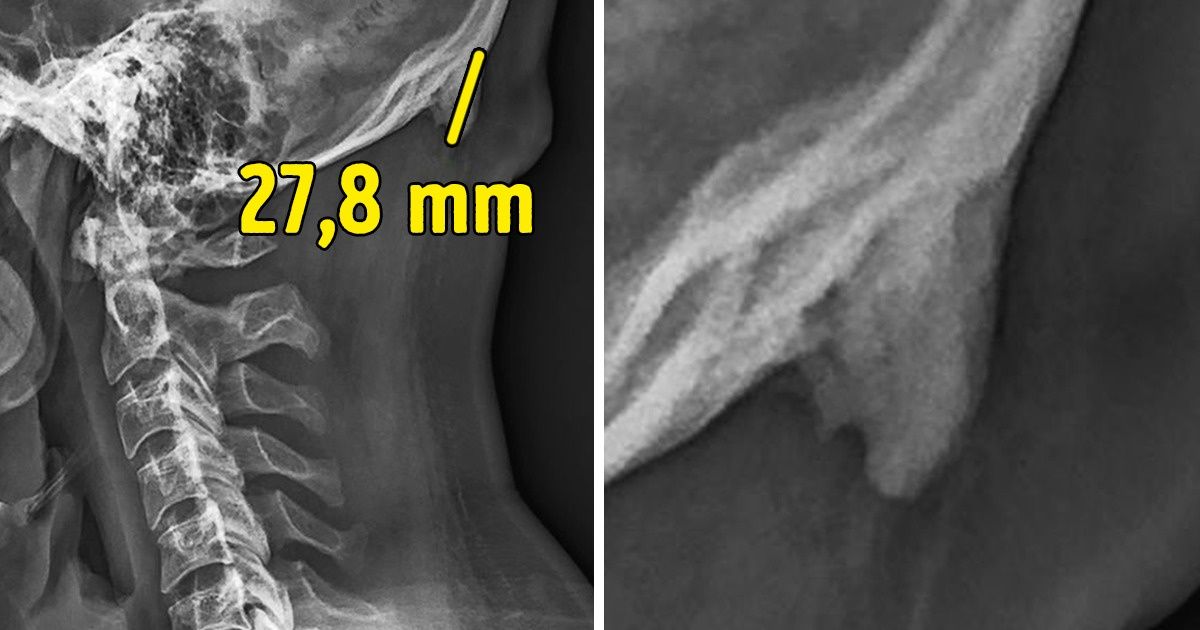

Estes cientistas desenvolveram um estudo no qual realizaram radiografias da cabeça e do pescoço de 1.200 pessoas entre os 18 e os 86 anos. As imagens mostraram que pelo menos 1 de cada 3 participantes, a maioria jovens, apresentava esse osso em forma de chifre na parte inferior do crânio. Denominaram-no de “protuberância occipital externa”, e às vezes era tão grande que podia chegar a mais de 3 cm de comprimento, sendo possível vê-lo e senti-lo na pele.